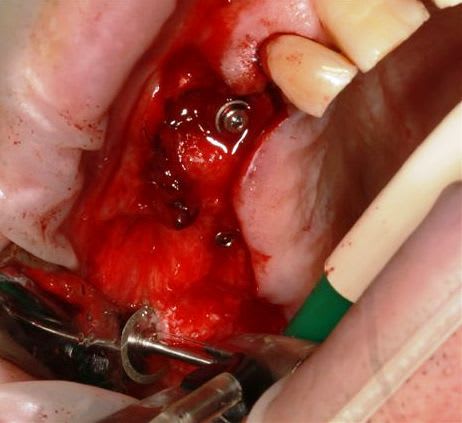

13 fenestration vestibulaire j'utilise la paroi palatine, lame N°15, spreader, expansion et pose d'un 40140

Puis 40120 en 15 avec léger SL, à l'ostéotome, et 40120 en 17.